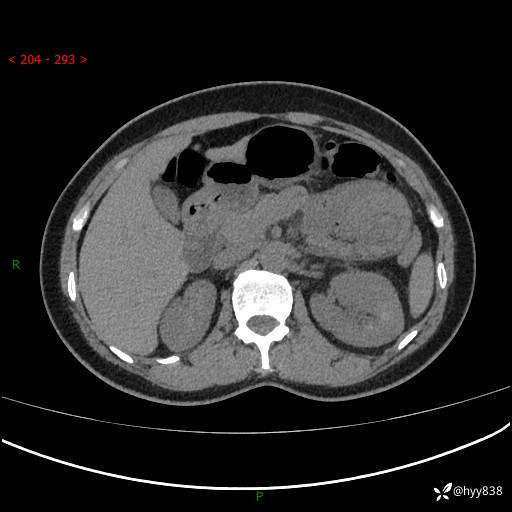

现病史:患者1天前无明显诱因下出现左上腹部及腰背部胀痛不适,阵发性加剧,伴肛门停止排气;无发热,无恶心呕吐,无畏寒发热,无心慌气短等不适,于当地市第二人民医院就诊,行腹部ct检查提示左上腹区肠系膜血管从剧聚集,分布紊乱伴肠管局限性稍扩张积液,不完全性肠梗阻;考虑子宫颈纳氏囊肿,双侧附件区囊状灶;予以抗炎及对症支持等治疗后未见明显缓解,现患者为求进一步治疗来我院急诊就诊,遂以“肠梗阻”收住入院。 病来,神志清,精神可,饮食睡眠不佳,经灌肠后排便2次,小便正常,体力体重无明显变化。

上腹部CT平扫